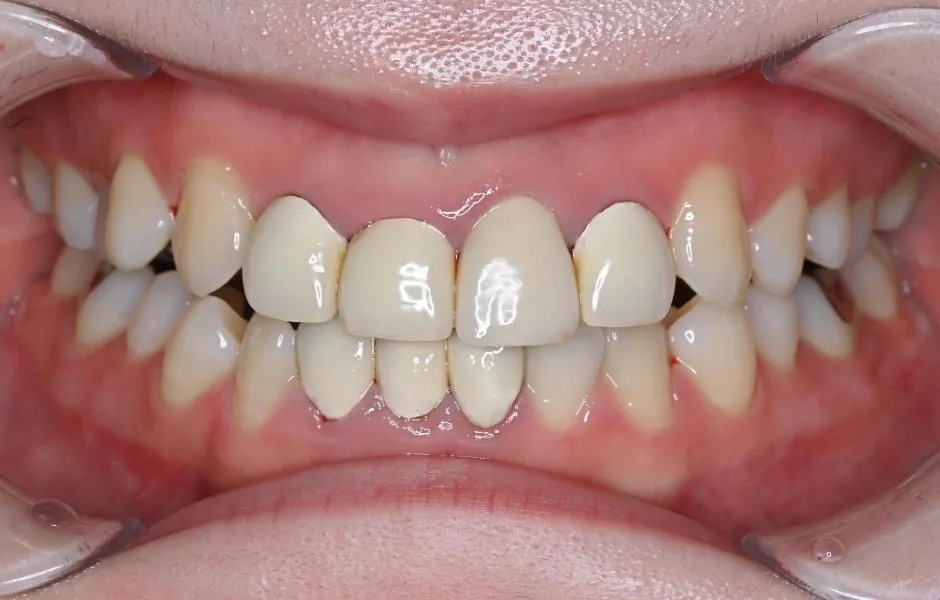

全顎治療・咬合治療

(歯がボロボロ)虫歯や歯周病が悪化して、歯を失っている・ボロボロのまま放置すると、機能性と審美性に影響がでます。お口のトラブルを改善できるよう、さまざまな治療をご提案します。

全顎治療・咬合治療(歯がボロボロ) -